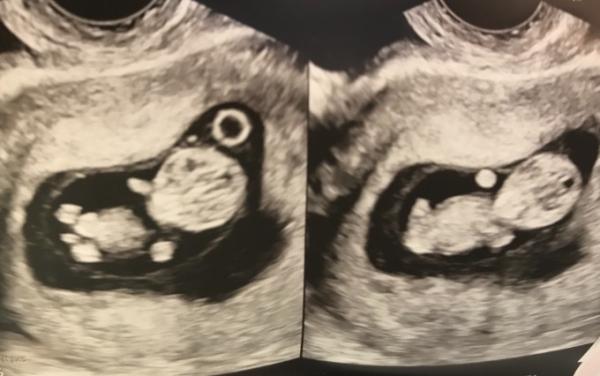

Hallo ihr Lieben, ich war am Dienstag bei 9+5 auch wieder beim Arzt und alles sieht gut aus!! Sogar wie ein kleiner Alien wie ich finde 3,2 cm ist mein Würmchen groß und hat schon fleißig gezappelt. Ich bin ganz verliebt. In 3 Wochen darf ich wieder hin, dann wird die Nackenfalte gemessen. Hoffe, dass alles gut ist. Hier noch ein Bildchen und keine Angst - ist nur eins. Hab zwei Bilder in einem bekommen

Wow!!!! So ein scharfes Bild hab ich ja noch nie gesehen, man sieht Arme und Beine so deutlich! Wahnsinn!